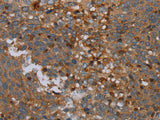

Applications IHC

IHC 1:50-1:200